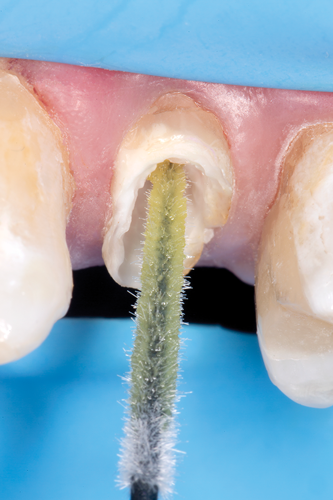

Fig 15. Flowable resin composite injected into the post channel using an angled tip.

Figure 15

Fig 16. Fiber post inserted into the post space to the base of the prepared channel.

Figure 16